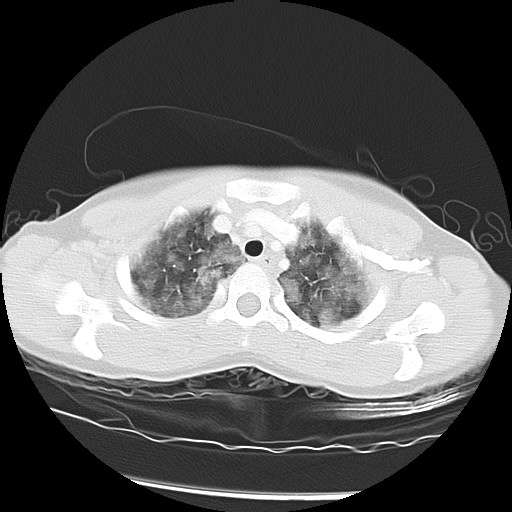

The following screen shows the images from the Chest CT:

| Figure 2-a | Figure 2-b | Figure 2-c |